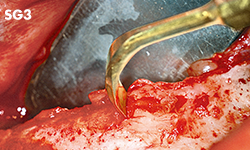

Escisiones en áreas con planos inclinados o proyecciones, o de difícil acceso con punta SG1 u otras puntas normales.

• POTENCIA [SURG] 80%

• Revestimiento de TiN

• Punta con curva a la derecha*

• Tres dientes; 0,6 mm de grosor

* La dirección del ángulo de la punta viene definida por la vista anterior de la punta.